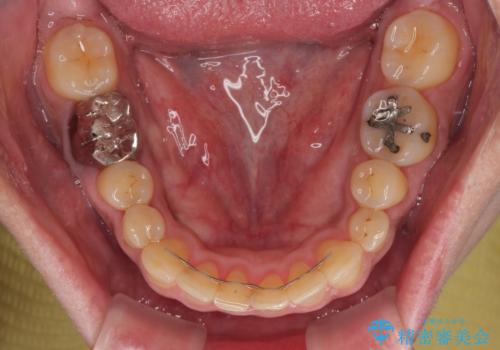

前歯の審美歯科治療 下顎の部分矯正と上顎前歯のオールセラミッククラウン

痛みが消えた後に、より目立たない装置をご希望とのことで、下顎前歯の舌側矯正で部分矯正を行い、歯列が整い、上顎前歯歯根部の病変が消退したことを確認した上で、上顎前歯をオールセラミッククラウンにて補綴治療を行うこととしました。

前歯部の見た目を改善するために、様々な医院を巡られたそうですが、当院ご提案のプランにて、痛みもスッキリと引いた、満足のいく仕上がりとなりました。